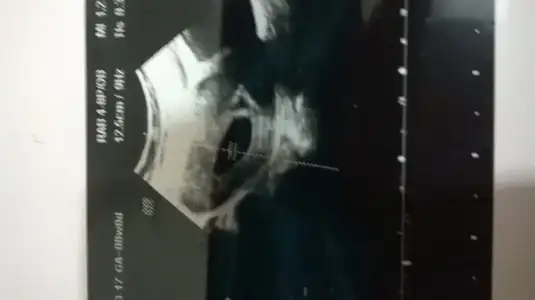

testleri tek tek çekmiştim 4 saatte bir yaptım zaten dün 14 de pozitif gibiydi sonra 6 tıda silikdi akşam yine öyleydi sabah 5.30 da koyuydu halada koyu kafam çorba gibi ben deneme yaptım zaten...

Foreverin de böyleydi.3 gun koyu olmuş test.3 gün de deneme yapmıştı.istersen oku onun geçmişten.oglu oldu maşallah.hayırlısı hazalcım.sen tevekkül et inşallah.